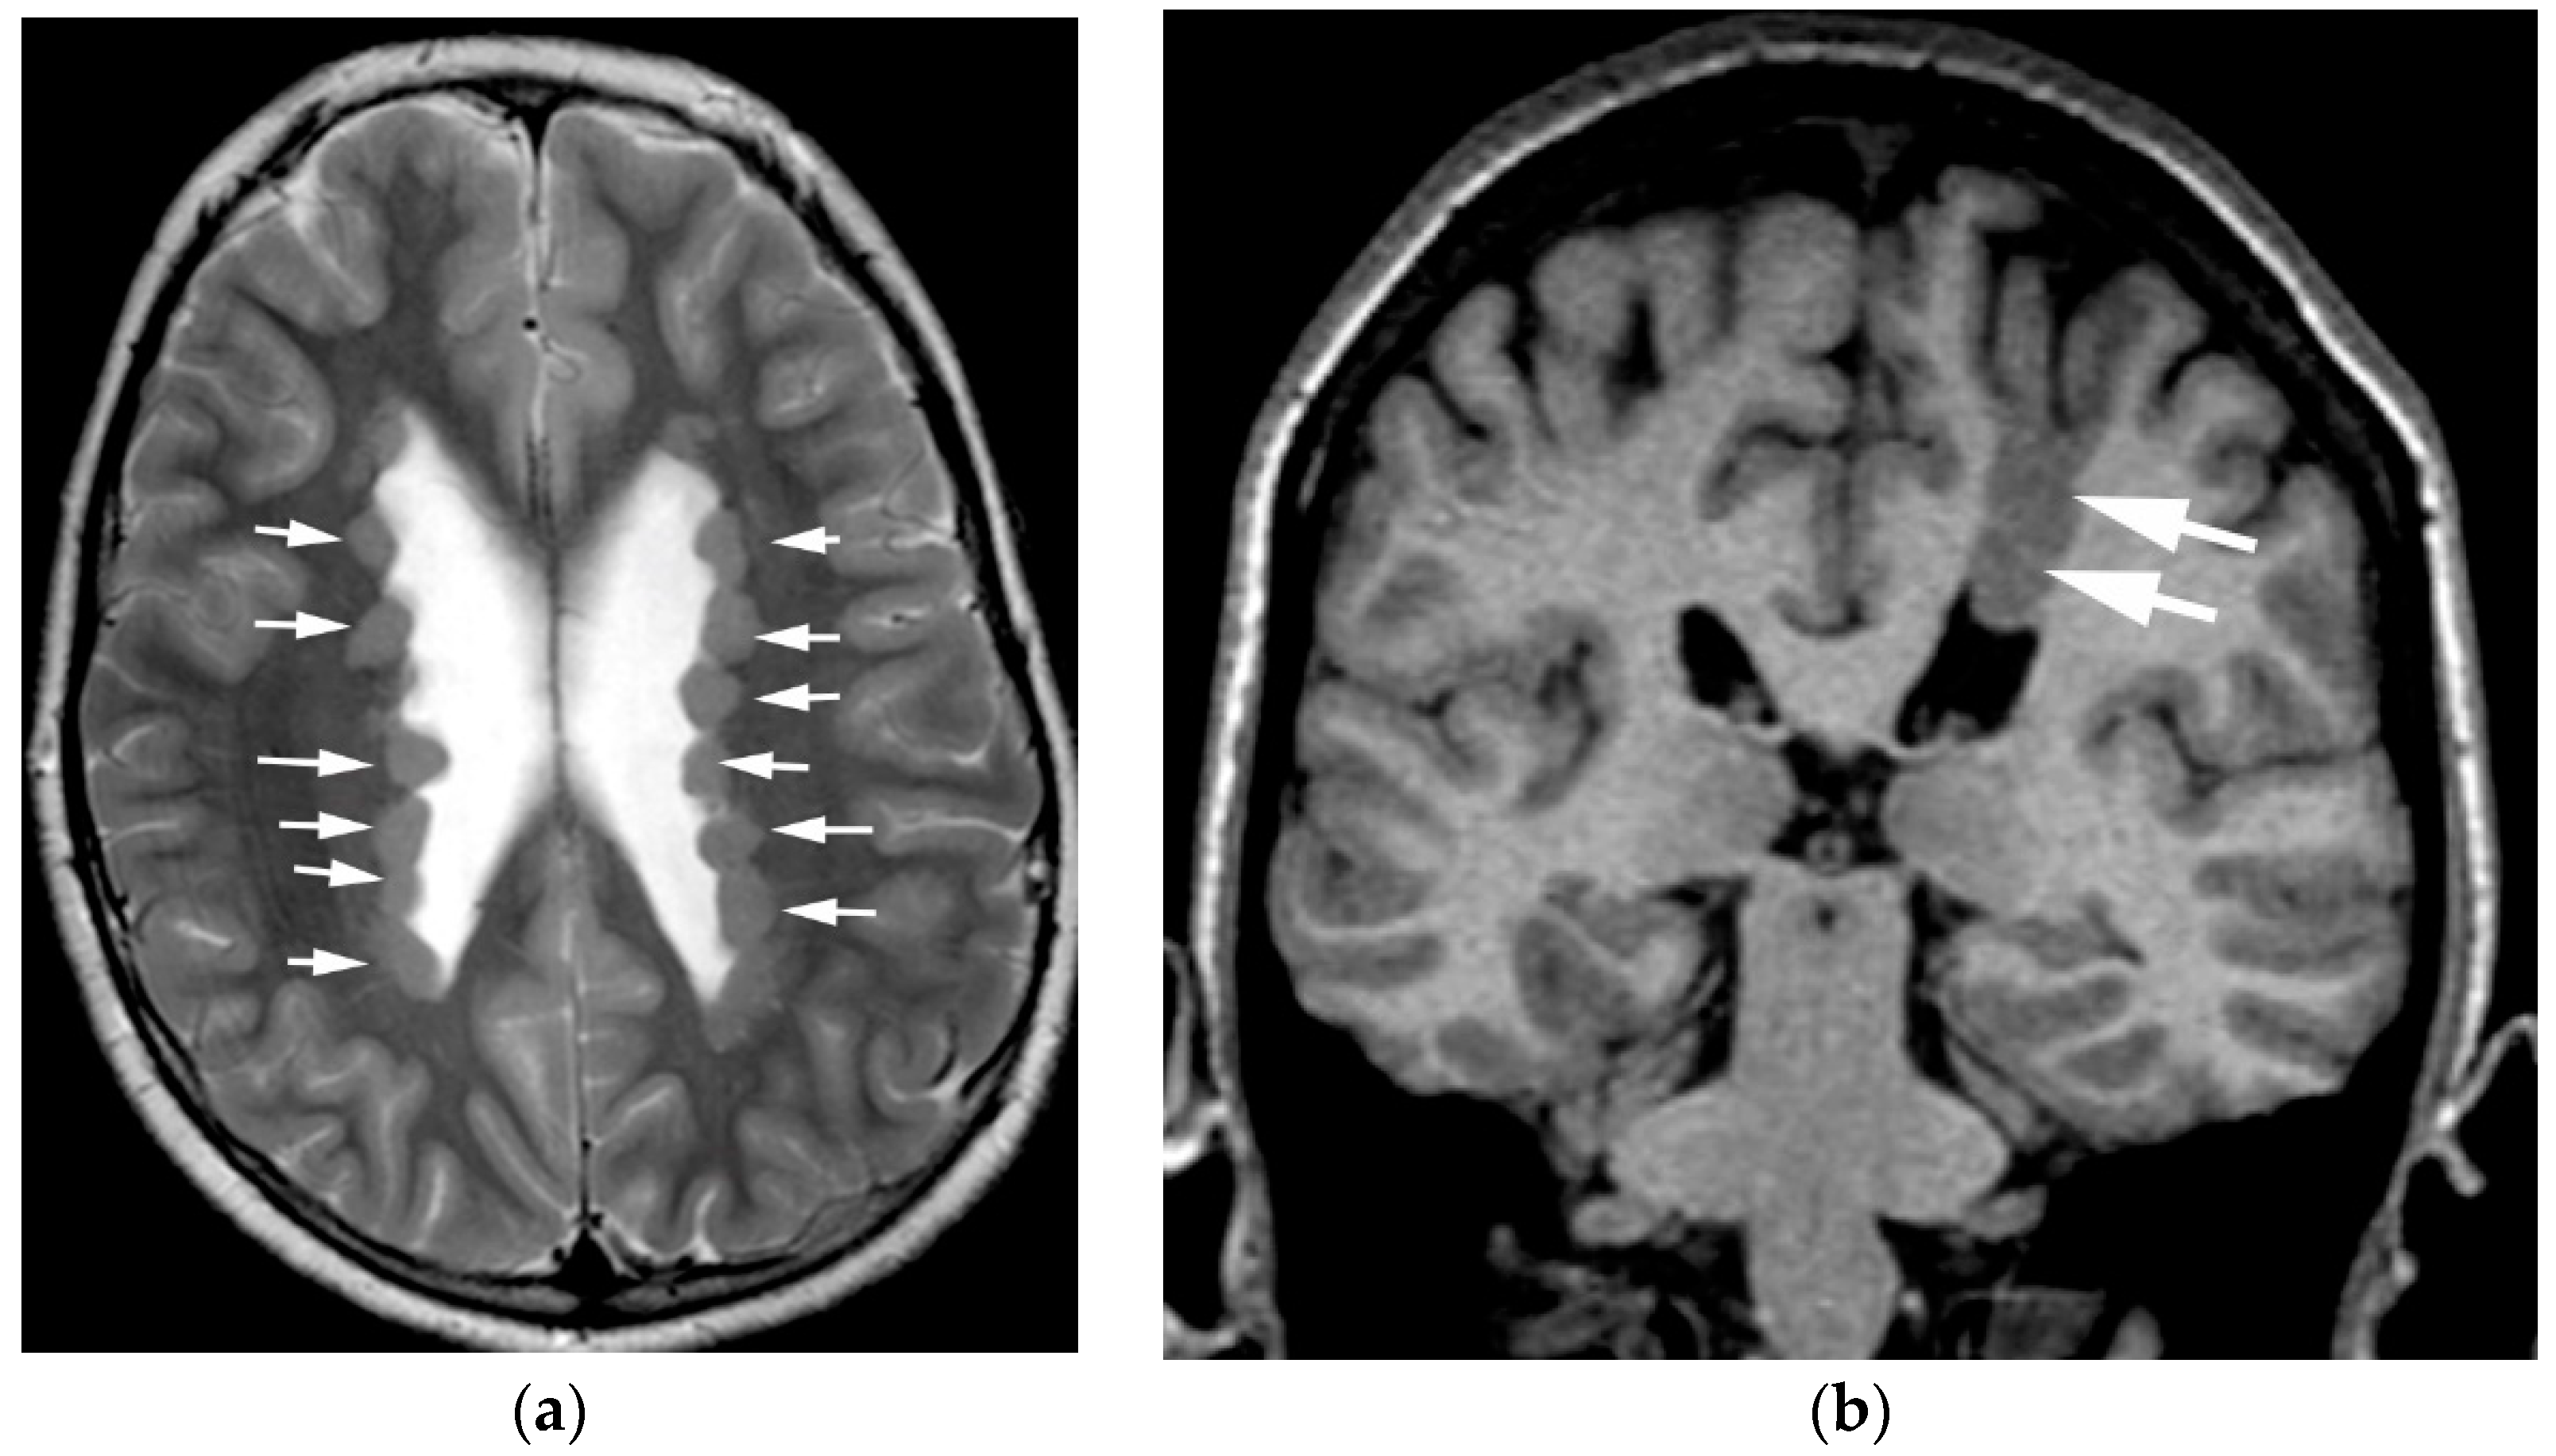

3.1. Heterotopia